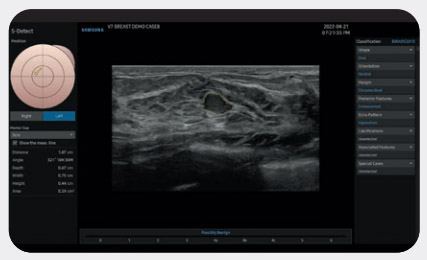

Анализ выбранных участков поражения в молочных железах и составление аналитического отчета

Функция S-Detect™ предназначена для анализа выбранных очагов поражения молочных желез. Отображая данные анализа, она позволяет оптимально организовать диагностику и получить отчет по стандартам BI-RADS ATLAS*.

* Система данных и отчетности по визуализации молочных желез. Atlas — зарегистрированный товарный знак компании ACR. Все права защищены компанией ACR.